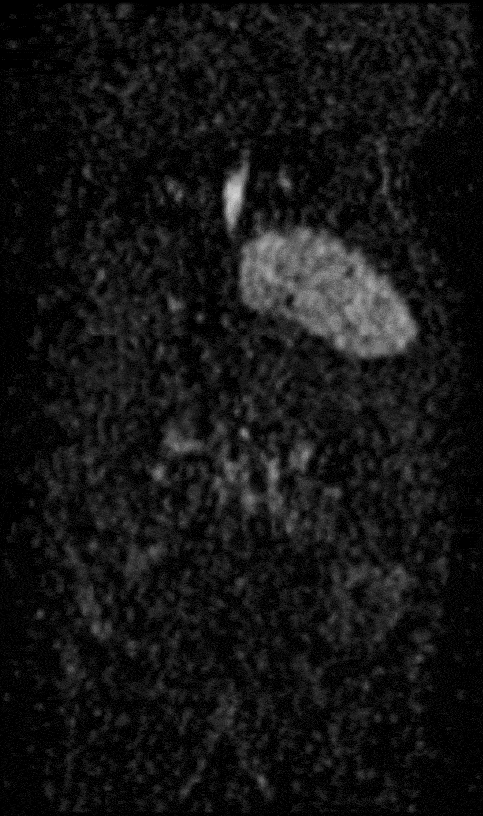

Multimodal Imaging: Multimodal imaging combines the strength of MRI with other imaging modalities such as PET and CT. PET provides information on the spatial distribution of molecular signal of interest. In this case MRI confirmed that the absence of tracer uptake in the center of the images was due to the presence of a necrotic core, which appears hyperintense on T2-weighted MRI.

Multimodal Imaging: Multimodal imaging combines the strength of MRI with other imaging modalities such as PET and CT. PET provides information on the spatial distribution of molecular signal of interest. In this case MRI confirmed that the absence of tracer uptake in the center of the images was due to the presence of a necrotic core, which appears hyperintense on T2-weighted MRI. Image Credit: Scintica Instrumentation Inc

Multimodal imaging combines the strength of MRI with other imaging modalities such as PET and CT. PET provides information on the spatial distribution of molecular signal of interest. In this case MRI confirmed that the absence of tracer uptake in the center of the images was due to the presence of a necrotic core, which appears hyperintense on T2-weighted MR.

Multimodal imaging combines the strength of MRI with other imaging modalities, such as PET and CT. PET provides information on the spatial distribution of molecular signal of interest. In this case MRI confirmed that the absence of tracer uptake in the center of the images was due to the presence of a necrotic core, which appears hyperintense on T2-weighted MR. Image Credit: Scintica Instrumentation Inc